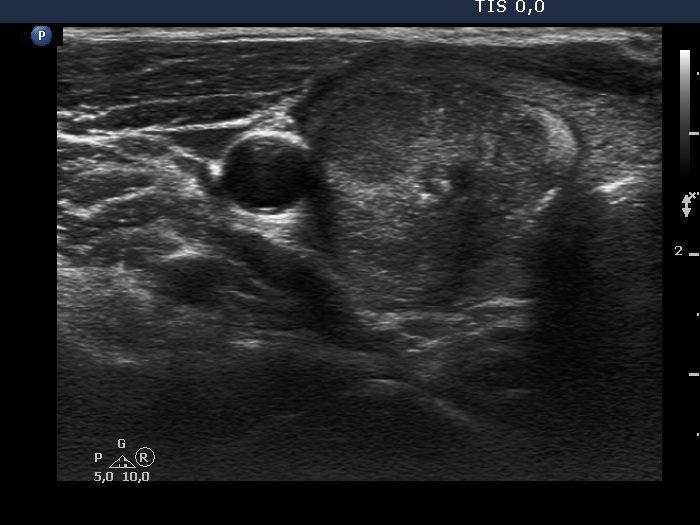

Ultrasonography. The thyroid was hypoechoic and presented with several discrete areas. A hypoechoic nodule occupied great part of the right lobe. The nodule had echonormal fields, microcalcifications and halo and presented perinodular blood flow.